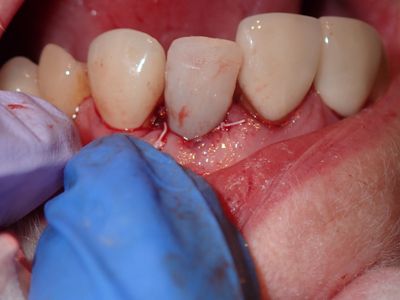

long root, atraumatic exo, loss of labial bone at apical end of socket, implant placed in ideal position, socket and buccal grafted with allograft and collagen membrane. Sutured prior to loading implant with screw-retained temp crown out of centric and protrusive occlusion

PA180025.JPG